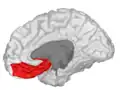

Orbitofrontal cortex

The orbitofrontal cortex (OFC) is a prefrontal cortex region in the frontal lobes of the brain which is involved in the cognitive process of decision-making. In non-human primates it consists of the association cortex areas Brodmann area 11, 12 and 13; in humans it consists of Brodmann area 10, 11 and 47.[1]

![]() Approximate location of the OFC shown on a sagittal MRI | |